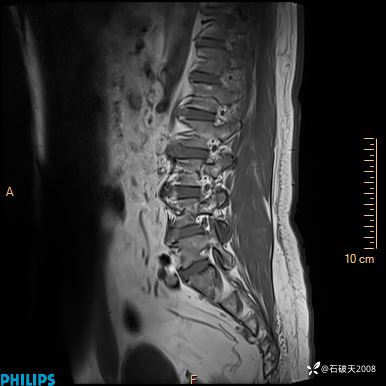

2023年3月份MRI影像

T1矢状位